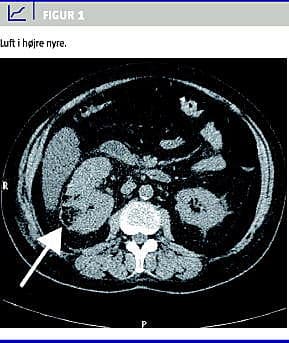

Objektivt: febrilia, sløret sensorium og smerter i abdomen lokaliseret til højre fossa. Paraklinisk: glukose 46 mikromol/l, leukocytter 15,5 × 109 /l, C-reaktivt protein (CRP) 7.248 mikromol/l, kreatinin 206 mikromol/l. Urinstiks: +blod, +ketoner, leukocyt- og nitritnegative. Patienten blev overflyttet til intensiv afdeling og behandlet for ketoacidose. CT af abdomen viste luft i højre nyres parenkym (Figur 1 ), luft i pelvis og i proksimale del af ureter. Ingen konkrementer eller hydronefrose.